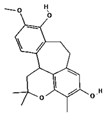

| Racemosol | 624971 | C21H24O4 | 340.4 | 0.36 | 0.55 | Yes |  |